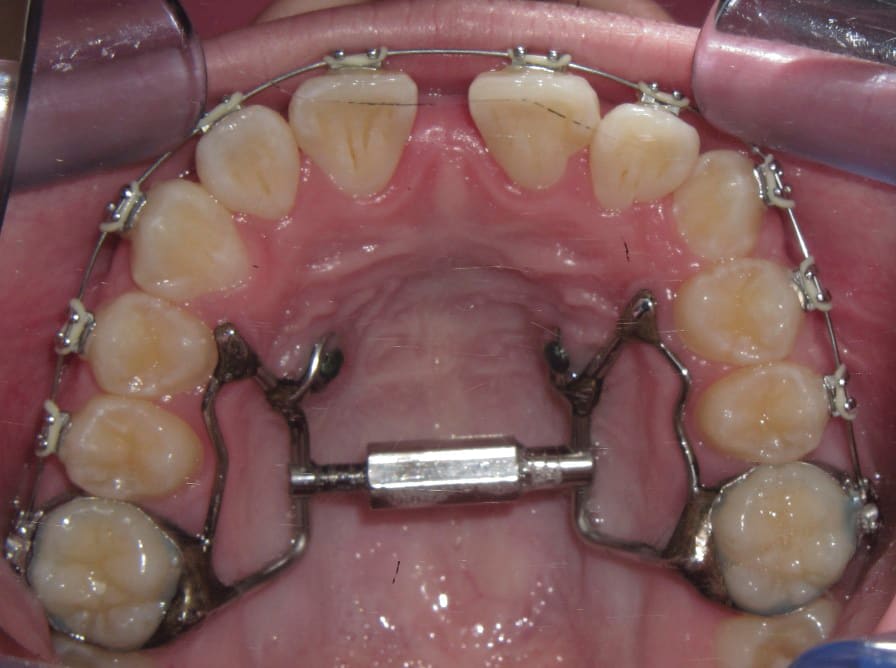

5. Any case that needs expansion of the maxilla. 3D imaging in these cases allow the orthodontist to determine if a cross bite is skeletal or dental. The clinician can readily determine if the molars are inclined in a cross bite or if the entire maxilla is constricted. This in turn can determine what forces are desirable to correct the cross bite. The 3D images also allow the clinician to evaluate the amount of bone around the roots of the teeth that are to be expanded. This also can aid the orthodontist in the type of forces to be utilized. Maybe bone augmentation is indicated in certain areas so as the roots are not once again fenestrated through the cortical bone creating a less stable environment. See Figure 18 through Figure 25. Figure 18 illustrates a maxilla that is constricted due to a narrow maxilla. Figure 19 illustrates the maxilla after expansion. Figure 22 illustrates a molar being tipped lingually. Thus a unilateral cross bite appliance was utilized.